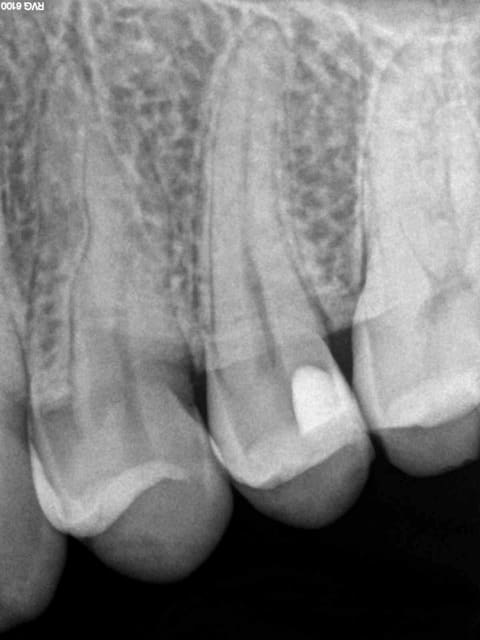

J'y travaille pour trouver un moyen simple et efficace pour poser la digue dans toutes les situations comme celle ci dessous. Tiens c'est tout frais, endo sc33 en 1 temps, 1H 15 et encore je n'ai pas d'assistante au fauteuil.

Pulpite indication endo. perte de substance: Indication onlay , mais pas dans le panier de soins donc sc 33, couronne coulée : patiente CMU.

Dis donc chicot t'es peut être le roi de l'endo mais au niveau économie tissulaire , ouverture de chambre , tu utilises un black et decker comme contre angle ?... t'y vas pas de main morte ... t'aurais peut être pu éviter le tenon alors , et qui sait la couronne .... et puis un genre screw post titane ? avec un matériau plastique perso je trouve pas ça terrible ... mais je ne suis qu'une petite dentiste qui utilise encore l'amalgame ... houuuu la méchante .....bon et puis la (ou le ) mitrailler comme ça pendant le soin juste pour nous montrer , faut pas tu sais , tu perds un temps fou ... après le temps de poster tout ça ..... t'imagines le temps perdu pour la rentabilité du cabinet ....